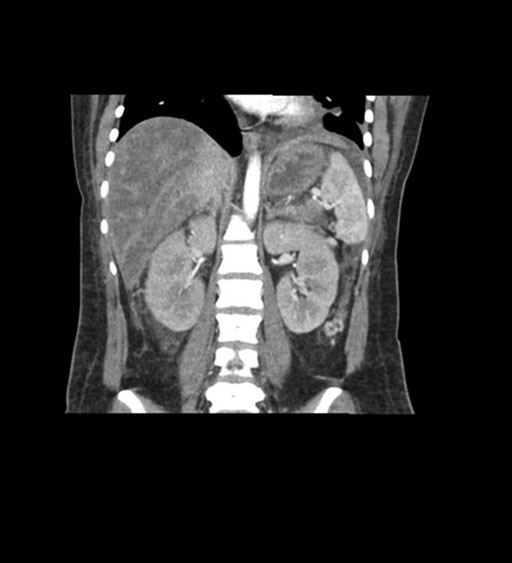

Coronal Venous